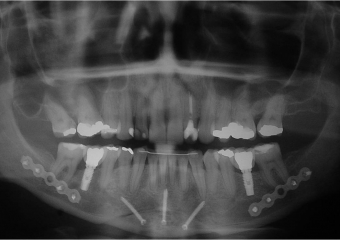

Raio x inicial

Telerradiografia inicial

Telerradiografia final